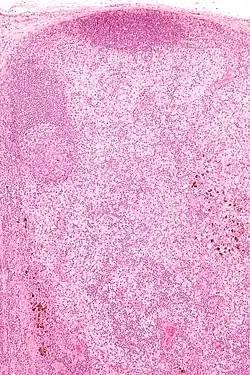

| Micrograph showing dermatopathic lymphadenopathy with the characteristic paracortical histiocytosis and melanin-laden macrophages. H&E stain. | |

Dermatopathic lymphadenopathy is diagnosed by a lymph node biopsy. It has a characteristic pattern of histomorphology and immunohistochemical staining:

- Paracortical histiocytosis

- Melanin-laden macrophages

- Eosinophils

- Plasma cells (medulla of lymph node)